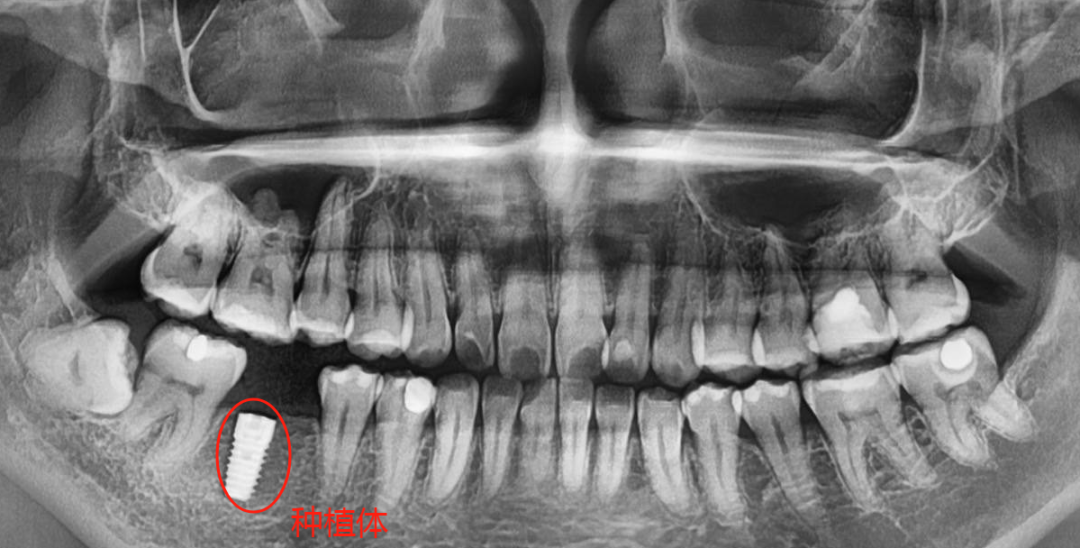

种植牙等修复体在口腔全景片上展现的通常是白色的,可以很清晰的看出来。另外补牙材料和金属或者全瓷牙冠也会显示出亮白色。